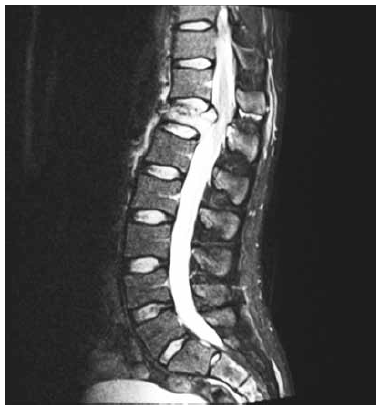

Paciente vítima de queda de moto com capacete, relatando fortes dores em região dorsal, sem deficits motores nem sensitivos ao exame clínico. Em investigação radiológica com tomografia e ressonância identificou-se fratura de corpo de T12 tipo compressão com comprometimento de muro posterior, lesão de ligamentos interespinhosos e supraespinhosos entre T11 e T12, conforme imagem a seguir.